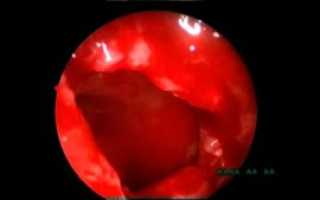

эндоскопическая гайморотомия

Эндоскопический доступ – это доступ без разрезов из полости носа или (реже) из полости рта. В стенке гайморовой пазухи делается прокол, через который в нее вставляется эндоскоп.

Прокол в диаметре составляет не более 5 мм. Изображение с микроэндоскопа передается на монитор и хирург имеет возможность видеть внутреннее строение пазухи в многократном увеличении.

С помощью специальных эндоскопических инструментов в пазухе проводятся все необходимые манипуляции (вычищение, удаление патологического содержимого, удаление полипов, кист, инородных тел, взятие материала на гистологическое исследование).

Вторая цель операции – это расширение естественных соустий пазухи с полостью носа для нормального дренирования пазухи в последующем.